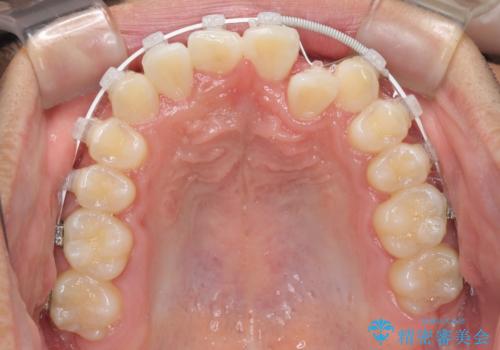

- 矯正装置

- 審美装置

- 治療計画

- 前歯のクロスバイトを気にして来院された患者様です。

歯がすり減って不揃いの形態となっていますが、まずは矯正治療によりクロスバイトを改善することとしました。

治療期間を極力短くしたいとのことで、ワイヤー矯正により治療を行うこととしました。

今後はすり減ってしまった歯の形をセラミッククラウンで改善したいとのことで、クロスバイトが改善し咬みやすくなった時点で装置を外すこととしました。

1年で治療を終えることができ、患者様には大変満足していただきました。